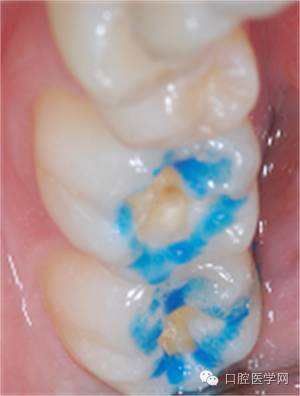

初始片

1、 评估牙体情况,患牙牙合面形态完整,可直接制作印章,若形成了破坏,可适当做一些形态补偿。

2、牙体颜色较为正常,简单比色后选用3M  Z350 body A3.5色,直接充填。

Z350树脂制作印章